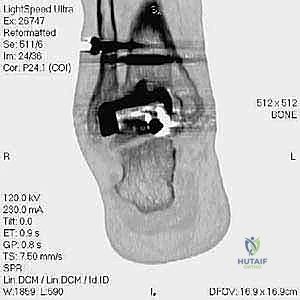

مراجعة مفصل الكاحل الصناعي هي إجراء جراحي ضروري لمعالجة المشاكل التي قد تنشأ بعد الجراحة الأولية، مثل كسور الكعبين أو عدم استقرار المفصل. يتضمن العلاج التشخيص الدقيق عبر الأشعة السينية والتصوير المقطعي، يليه التدخل الجراحي لتثبيت الكسور واستعادة وظيفة الكاحل، مع التركيز على التعافي المبكر.

تُعد جراحة مراجعة مفصل الكاحل الصناعي (Revision Total Ankle Replacement) من الإجراءات الجراحية المتقدمة والبالغة الدقة في عالم جراحة العظام الحديثة. لا تقتصر هذه الجراحة على مجرد استبدال مفصل تالف بآخر جديد، بل هي عملية إنقاذ معقدة للغاية تهدف إلى معالجة المشاكل الميكانيكية والبيولوجية التي تنشأ بعد الجراحة الأولية. من أبرز هذه المشاكل: الفشل الميكانيكي للمفصل، تحلل العظام (Osteolysis)، أو حدوث كسور معقدة في الكعبين (Malleolar Fractures) المحيطة بالمفصل الصناعي. يتطلب هذا الإجراء تقييماً سريرياً وشعاعياً دقيقاً يشمل التصوير المقطعي ثلاثي الأبعاد والأشعة السينية، يليه تدخل جراحي دقيق لاستعادة التوازن الحيوي والميكانيكي للكاحل والحفاظ على الطرف من البتر أو الدمج.

- التصوير المقطعي المحوسب (CT Scan): وهو الأداة الذهبية لتقييم "المخزون العظمي" (Bone Stock). يوضح بدقة حجم الأكياس العظمية ومقدار العظم المفقود الذي سيحتاج لترقيع.

علاج هذه الكسور يتطلب مهارة فائقة من الدكتور محمد هطيف، حيث يتم استخدام تقنيات الجراحة الميكروسكوبية وتثبيت الكسور باستخدام صفائح معدنية دقيقة ومسامير (Locking Plates) دون المساس بثبات المفصل الصناعي، أو يتم دمج علاج الكسر ضمن عملية مراجعة المفصل الكلية إذا كان المفصل نفسه تالفاً.